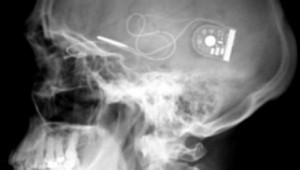

Το απίστευτα λεπτό και μικρό τσιπ που τοποθετήθηκε στο πίσω μέρος του ματιού των 2 ασθενών ανέλαβε να κάνει ακριβώς αυτή τη δουλειά. Τα 1500 φωτοευαίσθητα pixels, που έχει πάνω του, παίζουν πλέον τον ρόλο των ράβδων και των κώνων. Το φως που μπαίνει στο μάτι διεγείρει τα pixels, έτσι το μάτι το αντιλαμβάνεται, και στέλνει μήνυμα στο οπτικό νεύρο και από εκεί στον εγκέφαλο.

Ο καθηγητής Mac Laren τονίζει ότι: “είναι η πρώτη φορά που με την βοήθεια της τεχνολογίας καταφέραμε να επανενεργοποιήσουμε τον αμφιβληστροειδή, σε ανθρώπους που ήταν εντελώς τυφλοί. Πλέον μπορούν να αντιλαμβάνονται το φως που μπαίνει μέσα από το παράθυρο, καθώς και διάφορα σχήματα.

Μπορούν επίσης να ξεχωρίζουν τα έπιπλα και που βρίσκεται η πόρτα. Μέχρι στιγμής τα βλέπουν όλα ασπρόμαυρα αλλά είμαστε αισιόδοξοι ότι θα καταφέρουμε να τα βλέπουν και έγχρωμα…”